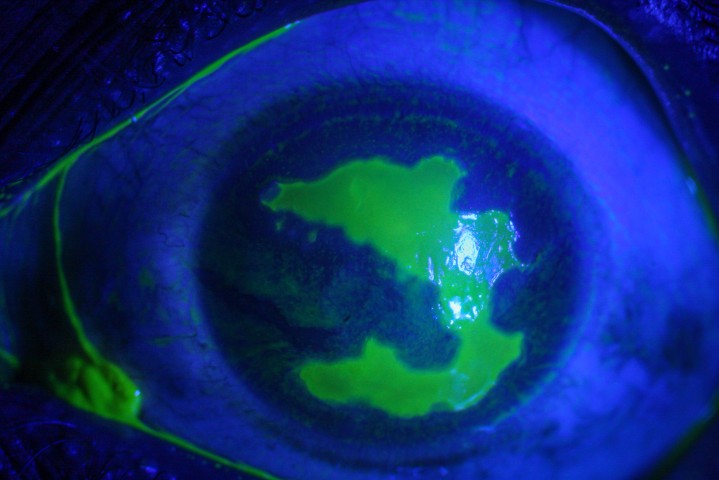

Current state of keratoconus management in New Zealand

By Drs Lize Angelo and Akilesh Gokul